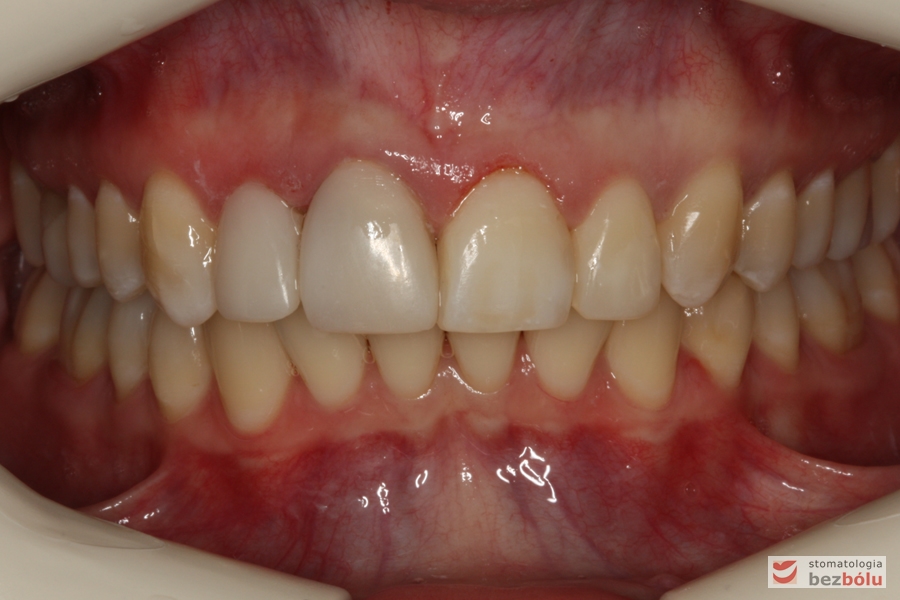

Pacjentka lat 26 zgłosiła się do gabinetu celem korekcji uśmiechu. Głównym zmartwieniem były problemy estetyczne, które znacznie wpływały na jakość życia pacjentki. Wykonano leczenie zachowawcze zębów oraz analizę cefalometryczną i analizę modeli diagnostycznych. Zaplanowano leczenie aktywne aparatem DAMON dla szczęki i żuchwy, które trwało 2 lata. Po fazie leczenia aktywnego rozpoczęto leczenie retencyjne z użyciem szyny tłoczonej dla szczęki i retainera stałego dla żuchwy.